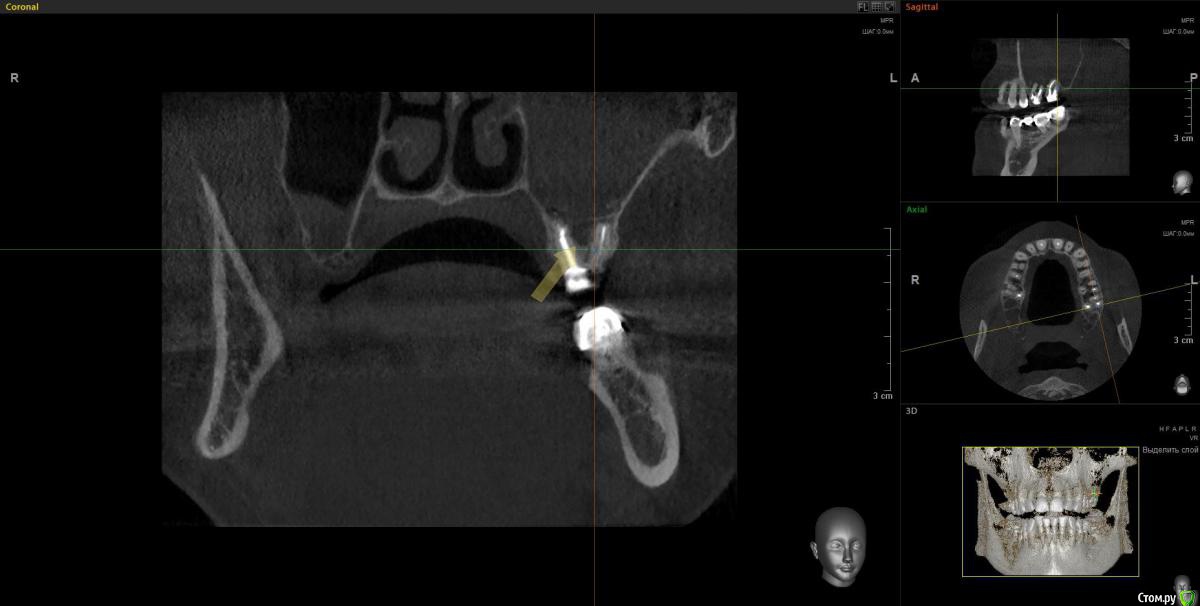

Doctor Vlad Опубликовано 14 апреля, 2020 Автор Поделиться Опубликовано 14 апреля, 2020 А дальнейшие планы каковы? Просто санация либо планируется реконструкция?Очень в тему вопрос. На работе задумался- а что дальше? и проблемка стала шире... как раз кт скинули. Там же не просто зашить и забыть там 2 импланта нужны)Кт до удаления месяца 2 назад. Стрелочка место где виднелась слизистая пазухи в момент удаления. по моим расчетам можно было бы без синуса если вся полость кисты заполнится костью, но теперь там будет скорей всего тяж или клапан этот. киста сама дно синуса приподняла. Ссылка на комментарий

Doctor Vlad Опубликовано 14 апреля, 2020 Автор Поделиться Опубликовано 14 апреля, 2020 Снимок до Ссылка на комментарий

Doctor Vlad Опубликовано 24 сентября, 2020 Автор Поделиться Опубликовано 24 сентября, 2020 27 удалил месяцев 3 назад, отмыл пазуху, зашил все заплаткой сст. сообщение закрылось. снимок кт свежий. хочу 2 импланта туда поставить. дефект костный дна синуса ламиной закрыть на винтах. все равно слой своей кости не велик, стружка понадобится. какие будут мнения? Ссылка на комментарий

Doctor Vlad Опубликовано 24 сентября, 2020 Автор Поделиться Опубликовано 24 сентября, 2020 (изменено) Самое главное забыл. кт свежее! и снимок на этапе зашивания соустья удаления 27 Изменено 24 сентября, 2020 пользователем Doctor Vlad Ссылка на комментарий